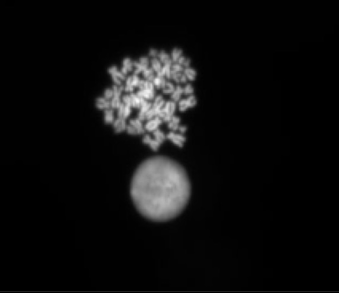

Hypotonic Soutions

Use of different hypotonics on a 47,XY, +21 lymphoblastoid cell line

courtesy of Ping Jin, Dr Jules Clyde and Helen Picton.

Dept Obstetrics and Gynaecology, University of Leeds

Buffered Hypotonic Solution

Potassium Chloride Solution

Optimal Hypotonic Solution